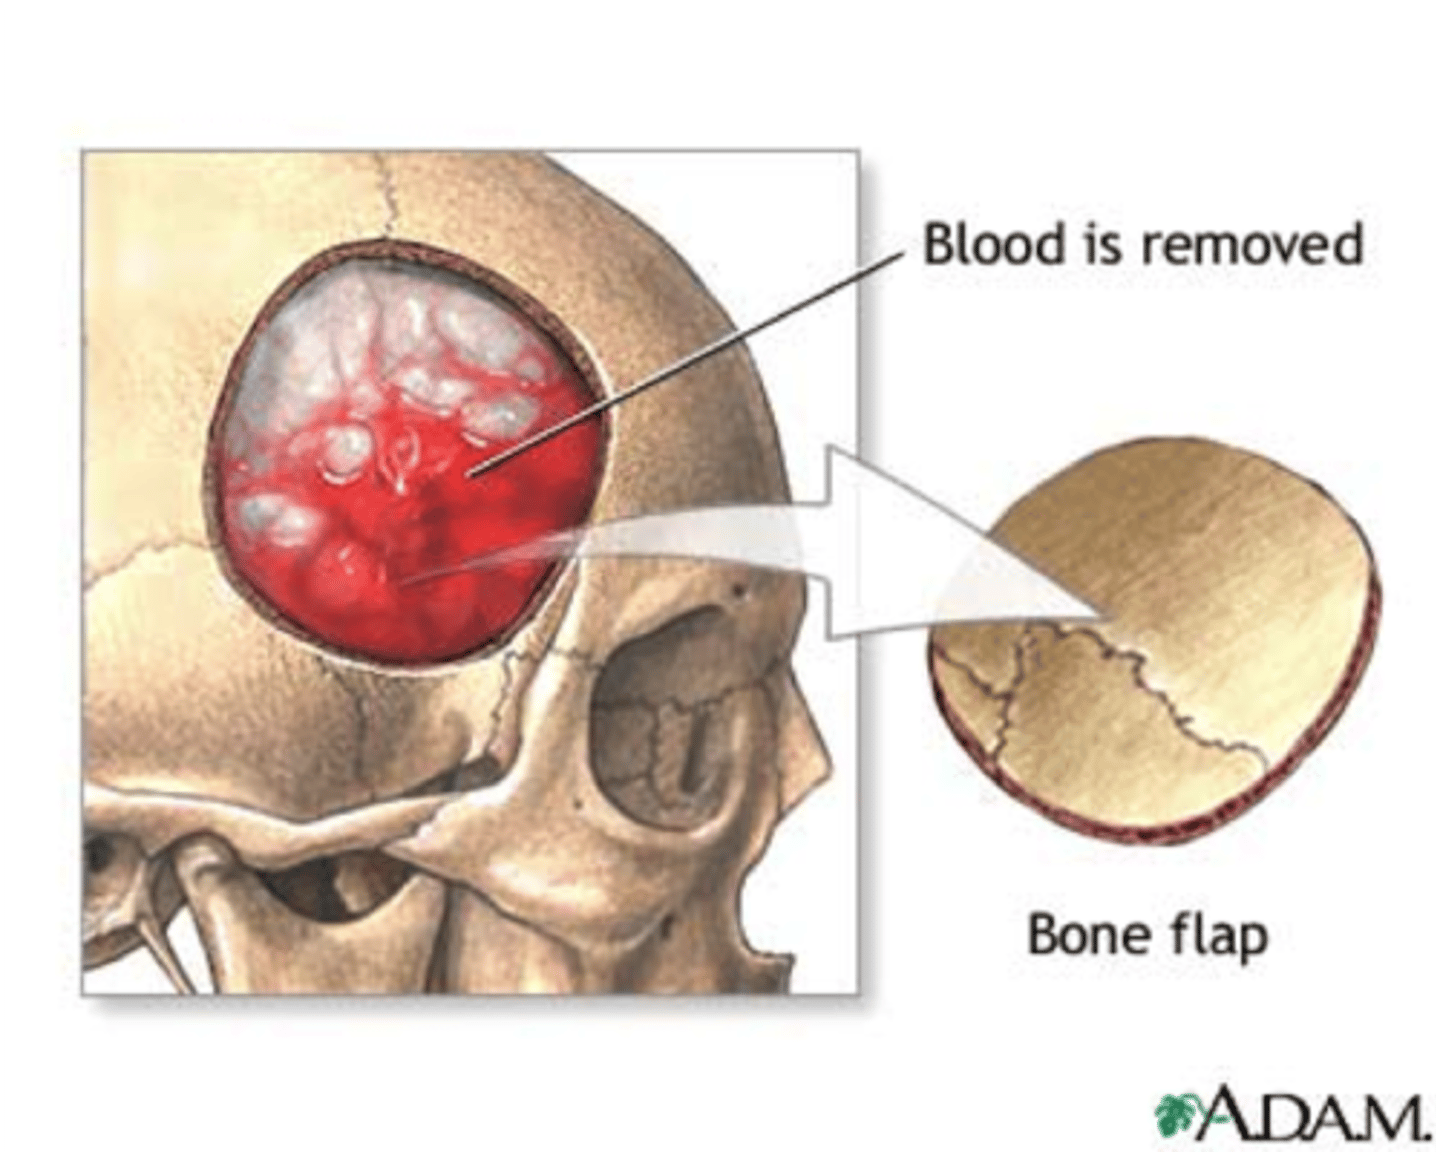

What is a craniotomy?

evacuate hematomas, remove bone fragments, remove foreign objects, by removing a portion of the skull to expose the brain